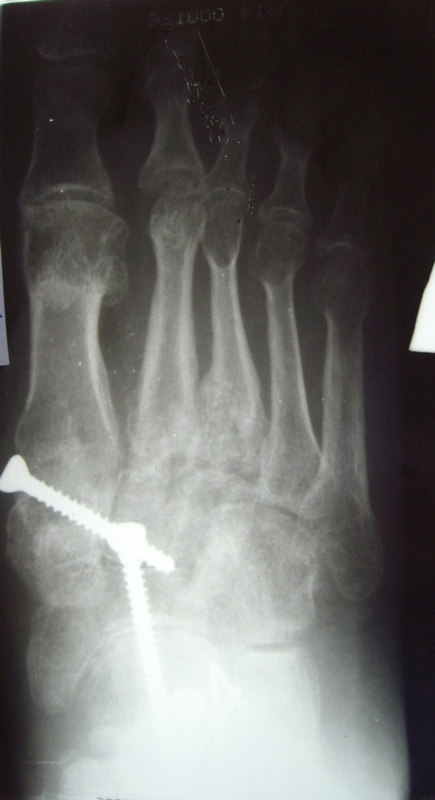

Лечился по поводу перелома D- 12 позвонка с нижним парапарезом и оскольчатых переломов плюсневых костей левой стопы. Производился остеосинтез переломов плюсневых костей левой стопы спицами.В 2007 году произведена стабилизирующая операция на позвоночнике с ламинэктомией и фиксацией металлоконструкцией и операция артродез левого голеностопного, подтаранного, таранно-ладьевидного, межклиновидных суставов с фиксацией винтами. В 2008 г. часть винтов удалена. Больной отмечает появление парестезий и движений в пальцах обеих стоп в этом году ( ежедневно пользуется миостимулятором Аб Троник).В настоящее время жалобы на деформацию и нестабильность в левой стопе, боль в области голеностопного сустава, в области пятки (проекция винта).

При осмотре имеется плоско-вальгусная деформация левой стопы, болезненность в пяточной области в проекции винта, тугоподвижность в области шопарова сустава. На тыльной поверхности рубцы. План лечений: удаление винта с подошвенной области, корригирующий реартродез в щопаровом суставе. Как удалить остатки винта? Возможно, понадобится реартродез голеностопного или подтаранного сустава.

Trauma in 2006 г.-falling from height. It was treated in occasion of fractur D-12 vertebra with bottom paraparesis and splintered fractures of metatarsal of left foot. The osteosynthesis of metatarsal bones was made by wires.

In 2007 stabilizing operation on a backbone with laminectomy and arthrodesis of ankle,subtalar, talo-navicular, intecuneiform joints with fixing by screws . In 2008 the part of screws is removed. The patient marks{celebrates} occurrence movements in fingers of both stop in this year.

At survey there is valgus and planus a deformation of left foot, morbidity in calcaneal area in a projection of the screw,the motion in the midfoot. There is the hems on a back surface of foot.

Здравствуйте!Мы в таких случаях удаляем металл.А затем устраняем с некоторой гиперкоррекцией(3-5гр),имеющиеся деформации стопы.В этом случае-приведение переднего отдела,отведение среднего,ротацию пятки,пронацию переднего отдела,вальгус пятки и эквинус стопы(примерно видно по снимкам).Так же по R-гр. видно ,что можно справиться закрыто(точнее после повторных R-гр).Работаем с аппаратами Илизарова.Фиксация 3мес.Со второго дня(п\о период)обучаем нормальной ходьбе с учетом биомеханики.